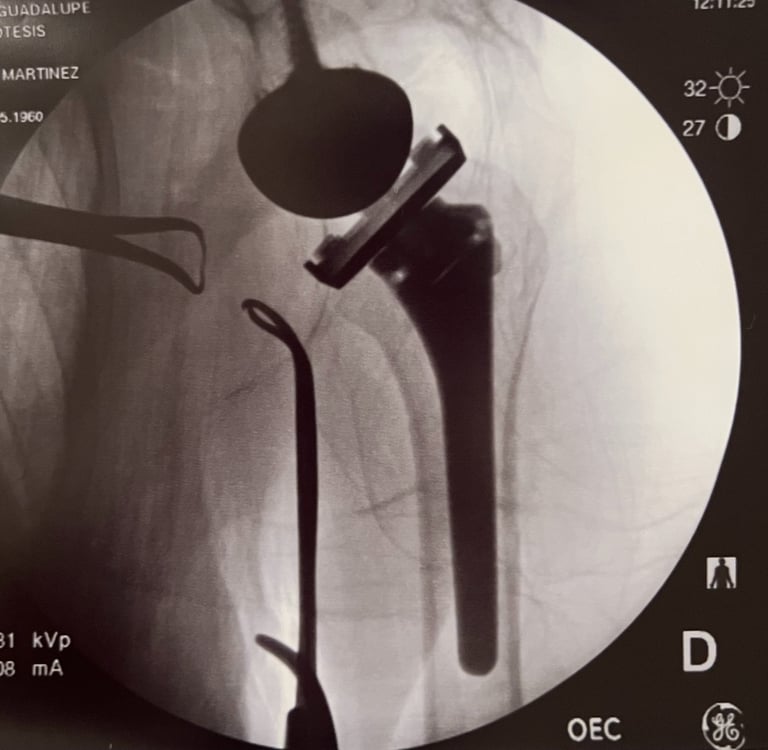

Control de radiografía de prótesis reversa de hombro.